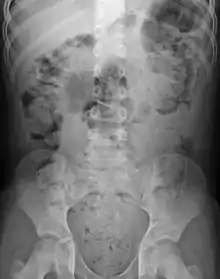

| Constipation in a young child seen on X-ray. Circles represent areas of fecal matter (stool is white surrounded by black bowel gas). | |

Abdominal X-rays are generally only performed if bowel obstruction is suspected, may reveal extensive impacted fecal matter in the colon, and may confirm or rule out other causes of similar symptoms.[24][16]